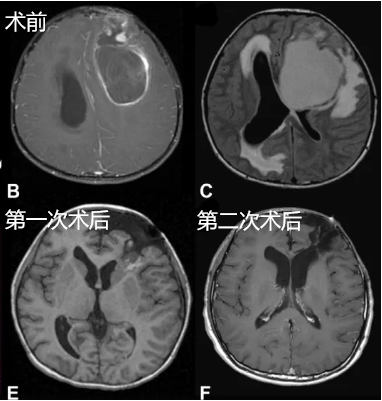

这样一个巨大的室管膜瘤盘踞在10岁的杰克脑中,令人触目惊心。连续三周的精神萎靡、运动迟缓以及间歇性的呕吐,让杰克深受折磨。然而,当父母一看到这幅惊人的影像时,更深的绝望笼罩在一家人心中:孩子还能活下去吗?

巨大的肿瘤已经造成严重的占位效应和脑积水,从影像上也可以看到广泛的室周和瘤周水肿,眼底检查图像更是显示明显的乳头水肿,这些都为手术带来巨大的困难。

所幸,杰克一家的主刀医生为Rutka教授,为了尽可能全切肿瘤,并保留杰克的神经功能,Rutka教授制定了一套更为个体化的治疗方案,包括分阶段的手术及术后放疗巩固效果,提升孩子预后的同时延缓复发。

很快,第一次手术正式开始,并成功切除了腔底部向侧脑室方向的部分肿瘤,取得的组织病理显示为间变性室管膜瘤。第二次手术,Rutka教授完成大面积的肿瘤切除。为了不损伤重要神经血管,保留杰克的神经功能,教授并未强行全切,因为对于神经外科手术来说,是否全切并非评判手术成功与否的标准,重要的是术者在切除范围和保障功能之间的博弈。

为了进一步巩固手术效果,Rutka教授为杰克制定了后续的放疗方案,这一缜密的治疗策略无疑为杰克带来了良好的生活质量,他的最后一次随访中也并未发现肿瘤复发的迹象。